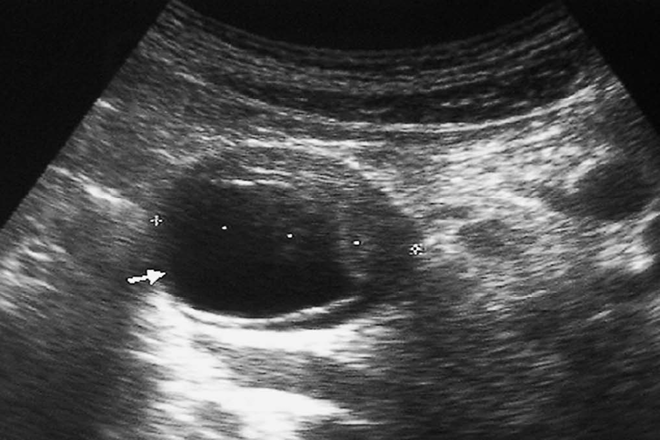

Radiológicamente, los abscesos se presentan como colecciones de tamaño variable, con paredes gruesas, que pueden contener gas y/o ecos internos, habitualmente acompañados de clínica infecciosa. También los quistes hidatídicos se muestran como quistes complejos. Desde el punto de vista clínico-radiológico, Howell. Recomienda la consideración de varios aspectos que nos harían dudar del diagnóstico de pseudoquiste, sin poder descartar etiología maligna de la colección pancreática. Los más relevantes son:   a) Ausencia de clínica compatible con pancreatitis, ya sea aguda, crónica o traumatismo pancreático.   b) Ausencia de cambios inflamatorios en el estudio tomográfico de la región pancreática.   c) Presencia de tabiques intracavitarios  ecográficamente podemos demostrar la morfología de la imagen quística anecogénica, de pared lisa y refuerzo acústico posterior. Durante su formación, el pseudoquiste puede tener ecos internos de aspecto complejo que desaparecen rápidamente al madurar. El detritus dentro de los pseudoquistes se evidencia por ecos dispersos de baja intensidad, secundarios a la degradación de células inflamatorias. Raramente se pueden observar calcificaciones en las paredes de pseudoquistes muy evolucionados. Habashi y Draganov  enfatizan que, durante las primeras fases del desarrollo de los pseudoquistes, estos pueden presentarse como lesiones complejas con diversos grados de ecos internos. Si bien desaparecen al tiempo en la mayoría de los casos, inicialmente pueden conducir a errores diagnósticos. Por lo general, esta apariencia es el resultado de la presencia de restos necróticos y es más común en pseudoquistes secundarios a pancreatitis aguda necrotizante que a pancreatitis crónica. Los pseudoquistes también pueden tener un aspecto complejo cuando se produce una hemorragia o infección en su interior, El estudio tomográfico se centra en la confirmación de la imagen redondeada de paredes finas en relación con el páncreas, de densidad cercana al agua y que puede acompañarse de signos inflamatorios pancreáticos con afectación de la grasa adyacente. Un 15% de los pseudoquistes se ubica en la cabeza del páncreas, mientras que el 85% restante se distribuye por el cuerpo y la cola. En el 70% de los casos, la CPRE puede identificar la comunicación entre el pseudoquiste y los conductos pancreáticos.